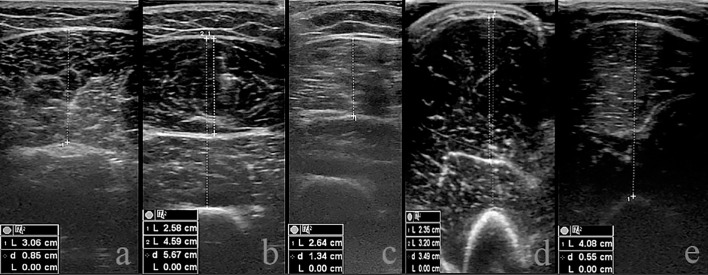

Objectives: The aim of the study is to compare the effects of low-intensity strength training applied with blood flow restriction (BFR) method to the lower and upper extremities with classical hypertrophy (CH) training on isokinetic strength parameters, muscle thickness (MT), and athletic performance.

Methods: The participants were divided into 2 groups as BFRG and CHG. The BFRG applied the strength training program with 20-40% of their 1 repetitive maximal (1 RM) and the CH with 60-80% of 1 RM for 8 weeks, including the lower and upper extremities. To analyze the results of different protocols (BFRG and CHG), as well as pre and post-test measurements and the protocol by time interaction effect, a repeated-measures two-way ANOVA test was employed.

Results: In both groups observed isokinetic strength parameters, MT and athletic performance were increased similarly (p<0.05).

Conclusions: BFR with low-intensity strength training elicits similar adaptations to that obtained with high-intensity strength training without BFR.